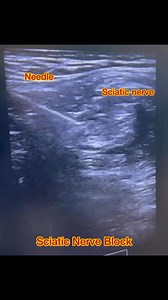

Anterior Approach - Ultrasound-Guided

Sciatic Nerve Block - Sciatic Saphenous Block

Ultrasound - Subgluteal Sciatic

Nerve Block - Sciatic